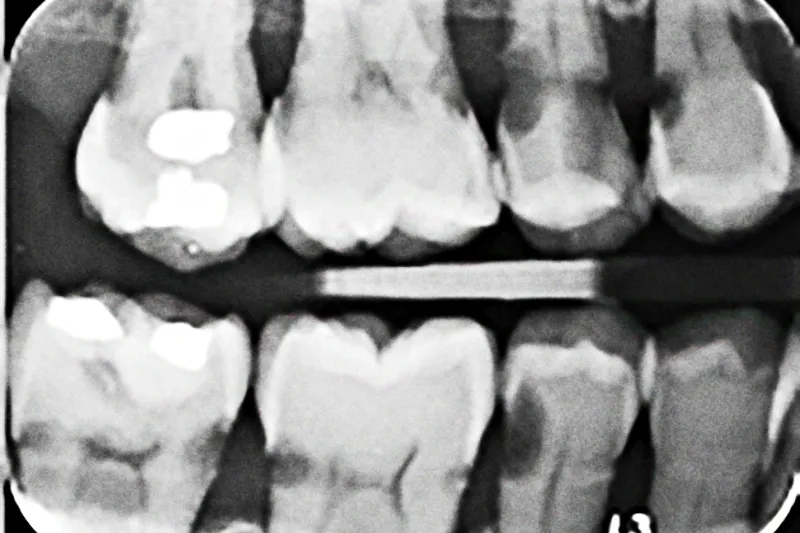

Patienttilfælde – En 73-årig mand rammes i 2010 af to blodpropper i hjernen. Patienten tilses af hjemmeplejen, indtil han i 2012 flytter på plejehjem. I løbet af 2-3 år udvikles mere end 20 carieslæsioner. Otte tænder ekstraheres, og øvrige carierede tænder restaureres med plastfyldninger. Der instrueres flere gange i hjemmetandpleje, og personalet på plejehjemmet forsøger at hjælpe med tandbørstning. Patienten er dog ikke samarbejdsvillig, formodentlig fordi han selv før sygdom har været vant til at klare den daglige mundhygiejne selv.

Case study – A 73-year-old man suffered from two strokes in 2010. After the strokes, the patient was taken care of by professional caretakers in his own home. The patient moved into a nursing home in 2012. During the following 2-3 years, more than 20 caries lesions developed. Eight teeth were extracted, and the rest of the decayed teeth were restored with composite fillings. The staff at the nursing home was instructed on how to help the patient with his daily oral hygiene. However, the patient was not willing to cooperate, presumably due to the fact that previously he was used to taking good care of his daily oral hygiene.